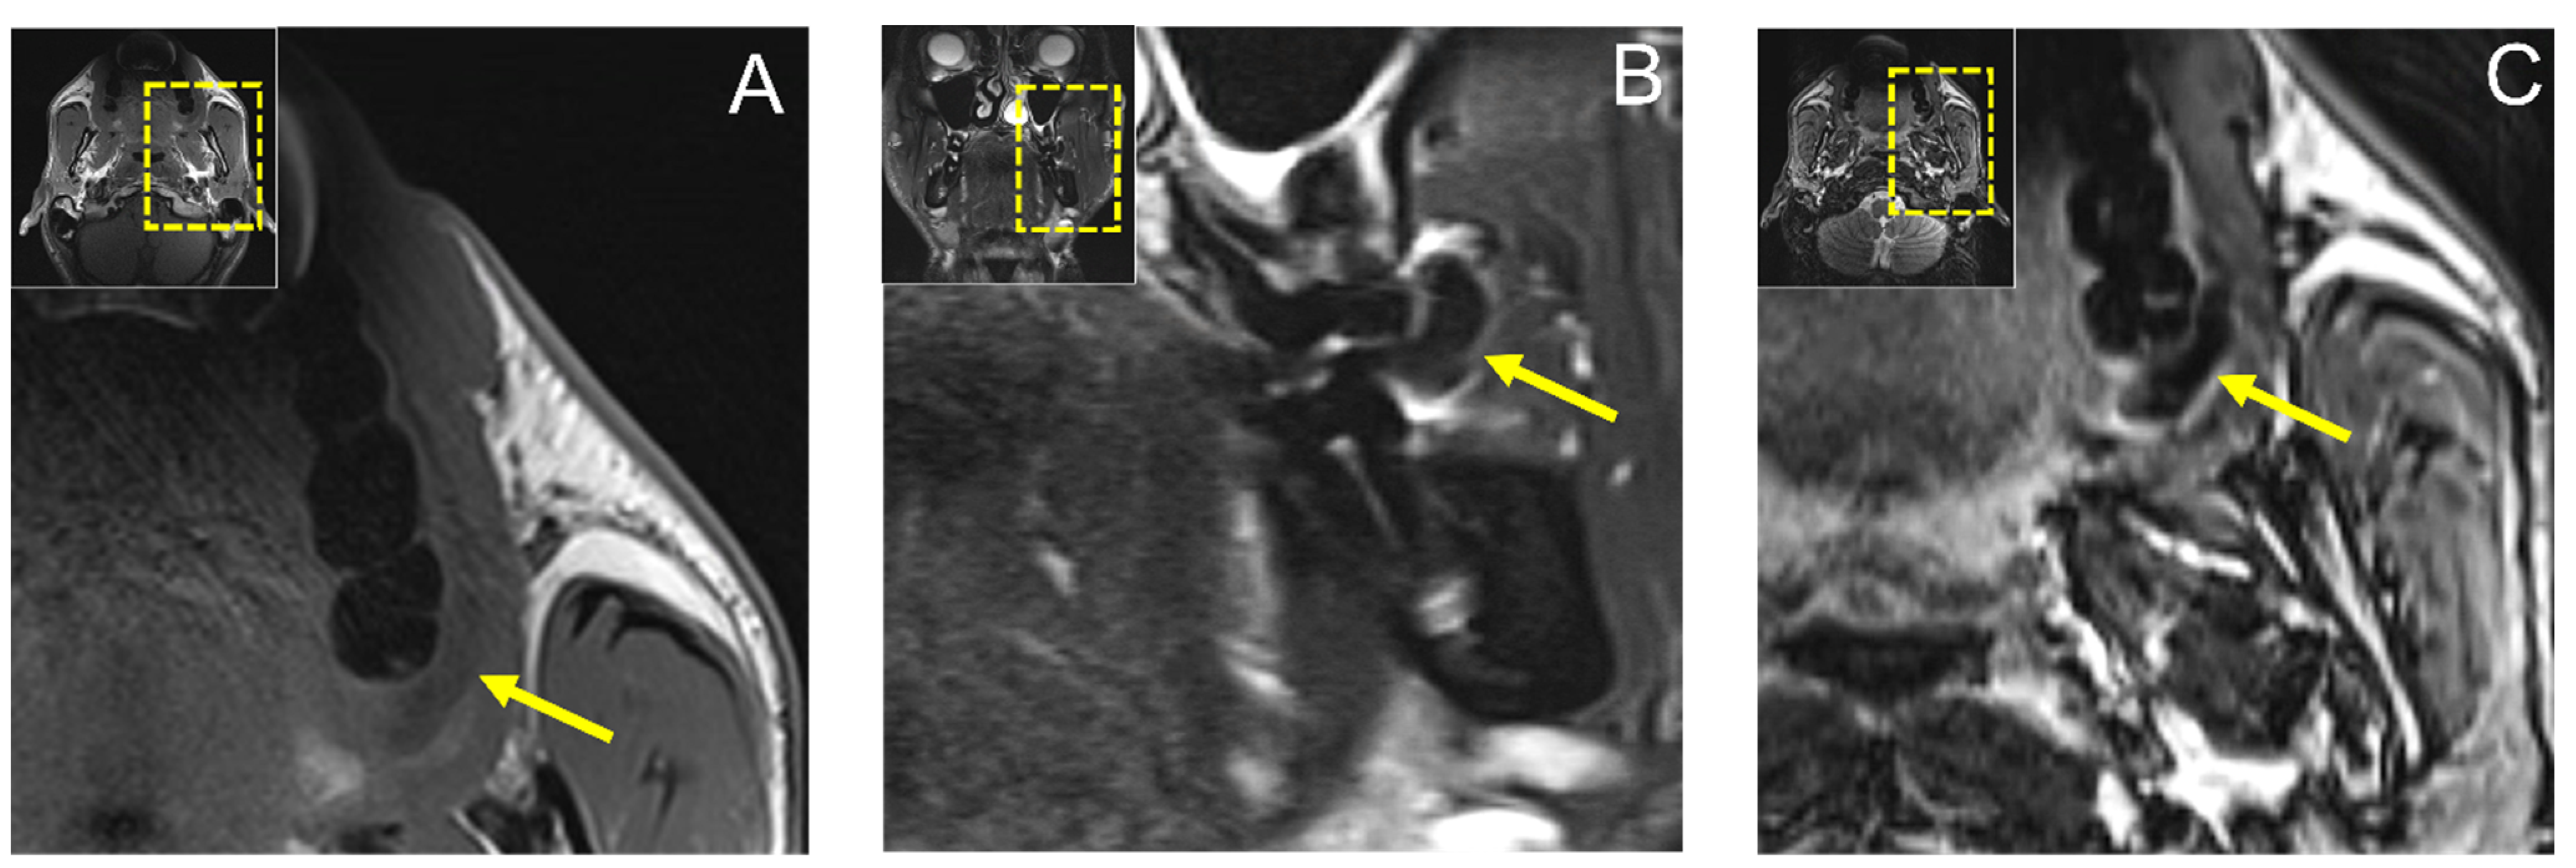

MR imaging with conventional noncontrast T1 and T2 fat-saturated (FS) turbo spin-echo (TSE) protocols revealed a hypointense lesion in T1-weighted images in the axial orientation measuring approximately 20 × 5 mm and a 12 × 8 mm hypointense lesion in the coronal T2 FS TSE reconstruction, ruling out a fat-containing tumor or cystic process (Figure 3).

Figure 3.

(A) Axial reconstruction of native T1 and (B) coronal reconstruction of T2 fat-saturated (FS) Turbo Spin-Echo (TSE) MRI protocols showing a hypointense lesion in T1-weighted images in axial orientation measuring approximately 20 × 5 mm and a 12 × 8 mm hypointense lesion in coronal T2 FS TSE reconstruction, ruling out a fat-containing tumor or cystic process. In addition, (C) axial T2-weighted Dixon TSE reconstruction is shown.